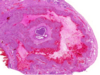

באיזה שלב הביצית בתמונה?

mature graafian follicle

מה גורם לביוץ?

LH הפרשה חדה של

ביצית יוצאת יחד עם הקורונה רדיאטה, שאר תאי ה

theca

והרגנולוזה נשארים בשחלה ומסתדרים מחדש.